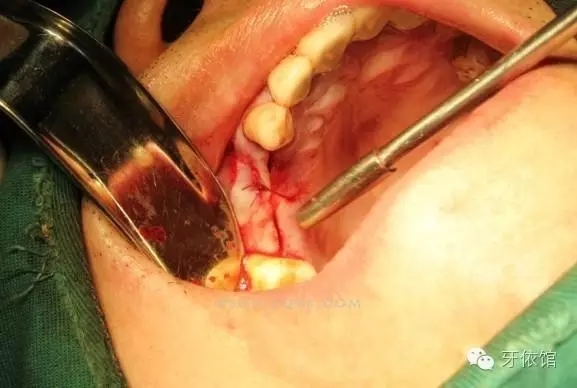

切開翻瓣

右上4,6牙位定位,先鋒鉆鉆至距離上頜竇底1-2mm處,改用CAS鉆穿透一個窩洞竇底。